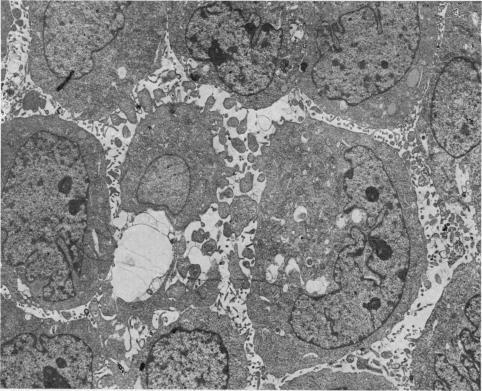

源自人移行细胞癌的细胞系的超微结构、核型分析及免疫学研究

Ultrastructure, karyology and immunology of a cell line originated from a human transitional-cell carcinoma.

A cell line (J82) was derived from a poorly differentiated, invasive, transitional-cell carcinoma, Stage T3. The cells have been propagated in vitro for 5 years and showed 100% aneuploidy and a mixed epithelial-fibroblastic morphology. The majority of cells contained 2Y chromosomes and several distinctive markers. Peripheral-blood lymphocytes from the donor of the J82 cells were tested sequentially for cytotoxicity toward autologous and allogeneic tumour cells. Autologous cytotoxicity was detected against J82 cells in early in vitro passage. Allogeneic lymphocytes from some patients with transitional-cell carcinoma were also cytotoxic to J82 cells in primary culture. However, selective cytotoxicity by lymphoid cells from bladder-carcinoma patients was not detected against J82 cells in long-term tissue culture.

摘要